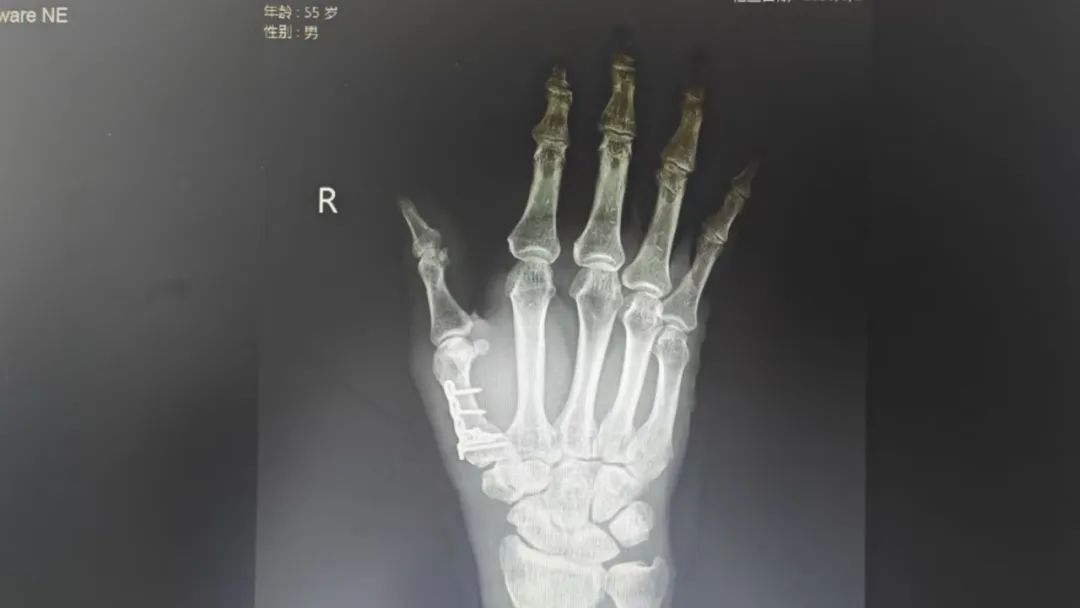

面对复杂的关节内骨折,骨科团队在三维CT重建中反复推演:如何以最小创伤实现解剖复位?如何避开神经血管丛精准固定?3月25日,一场“精微艺术”在无影灯下展开:

利用迷你钢板跨越骨折线,重建掌腕关节稳定性;

术中C臂机实时监测,确保关节面平整度误差<0.5mm;